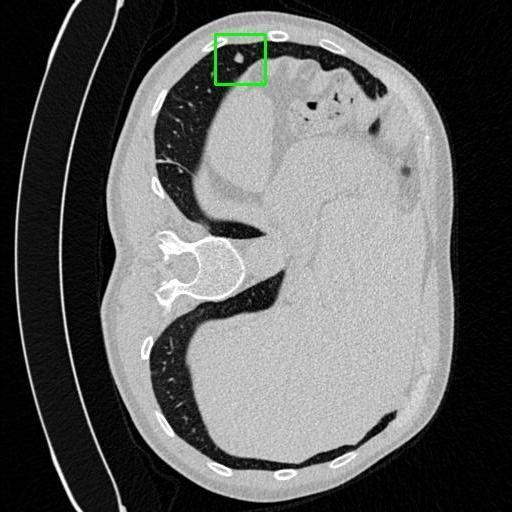

We developed an AI-based system using deep learning models for analyzing lung CT scans to detect and classify pulmonary nodules. We chose the YOLOv11 architecture for its enhanced object detection capability and adapted it specifically for medical imaging, incorporating pixel-level precision and severity classification.

Classification into three severity levels with colored bounding boxes.

Designed a severity classification system that categorizes nodules into null, moderate, and severe using colored bounding boxes, assisting in rapid clinical decision-making.